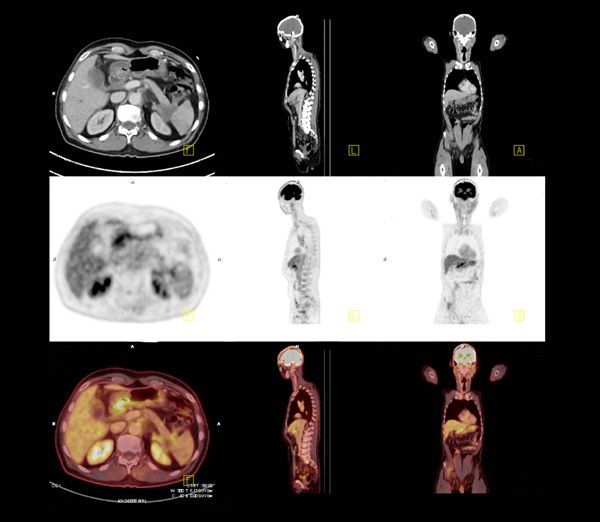

それらに比べ、やや地味な治療法なのが、希林さんが主に受けていた放射線治療だろう。放射線治療は、「がんを根こそぎ退治」というイメージよりは、「進行を遅らせる」「痛みを減らす」といったイメージに近い治療法である。手術ほど体力を消耗しないので、「仕事の合間に照射」といった小回りの効く治療ができる。

彼女が長く活躍できたのも、この放射線治療を上手く取り入れて、奏功した結果だろう。特に2011年の東日本大震災での原発事故以降、日本中にアンチ放射能ムードが広まる中で、雑音に惑わされず冷静に放射線治療を続けたことが生涯現役を貫くことができたコツだったように思う。